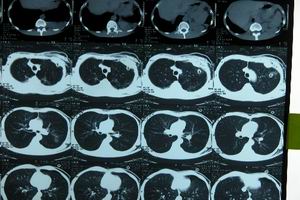

2.CT對胸腔內少量氣體的診斷較為敏感。對反覆發作的氣胸、慢性氣胸者觀察肺邊緣是否有造成氣胸的病變,如肺大泡、胸膜帶狀粘連,肺被牽拉、裂口不易閉合等。氣胸基本表現為胸膜腔內出現極低密度的氣體影,伴有肺組織不同程度的壓縮萎縮改變。

3.胸膜腔造影此方法可以明了胸膜表面的情況,易於明確氣胸的病因。當肺壓縮面積在30%~40%時行造影為宜,肺大泡表現為肺葉輪廓之內單個或多個囊狀低密度影;胸膜裂口表現為冒泡噴霧現象,特別是當患者咳嗽時,由於肺內壓增高,此徵象更為明顯。